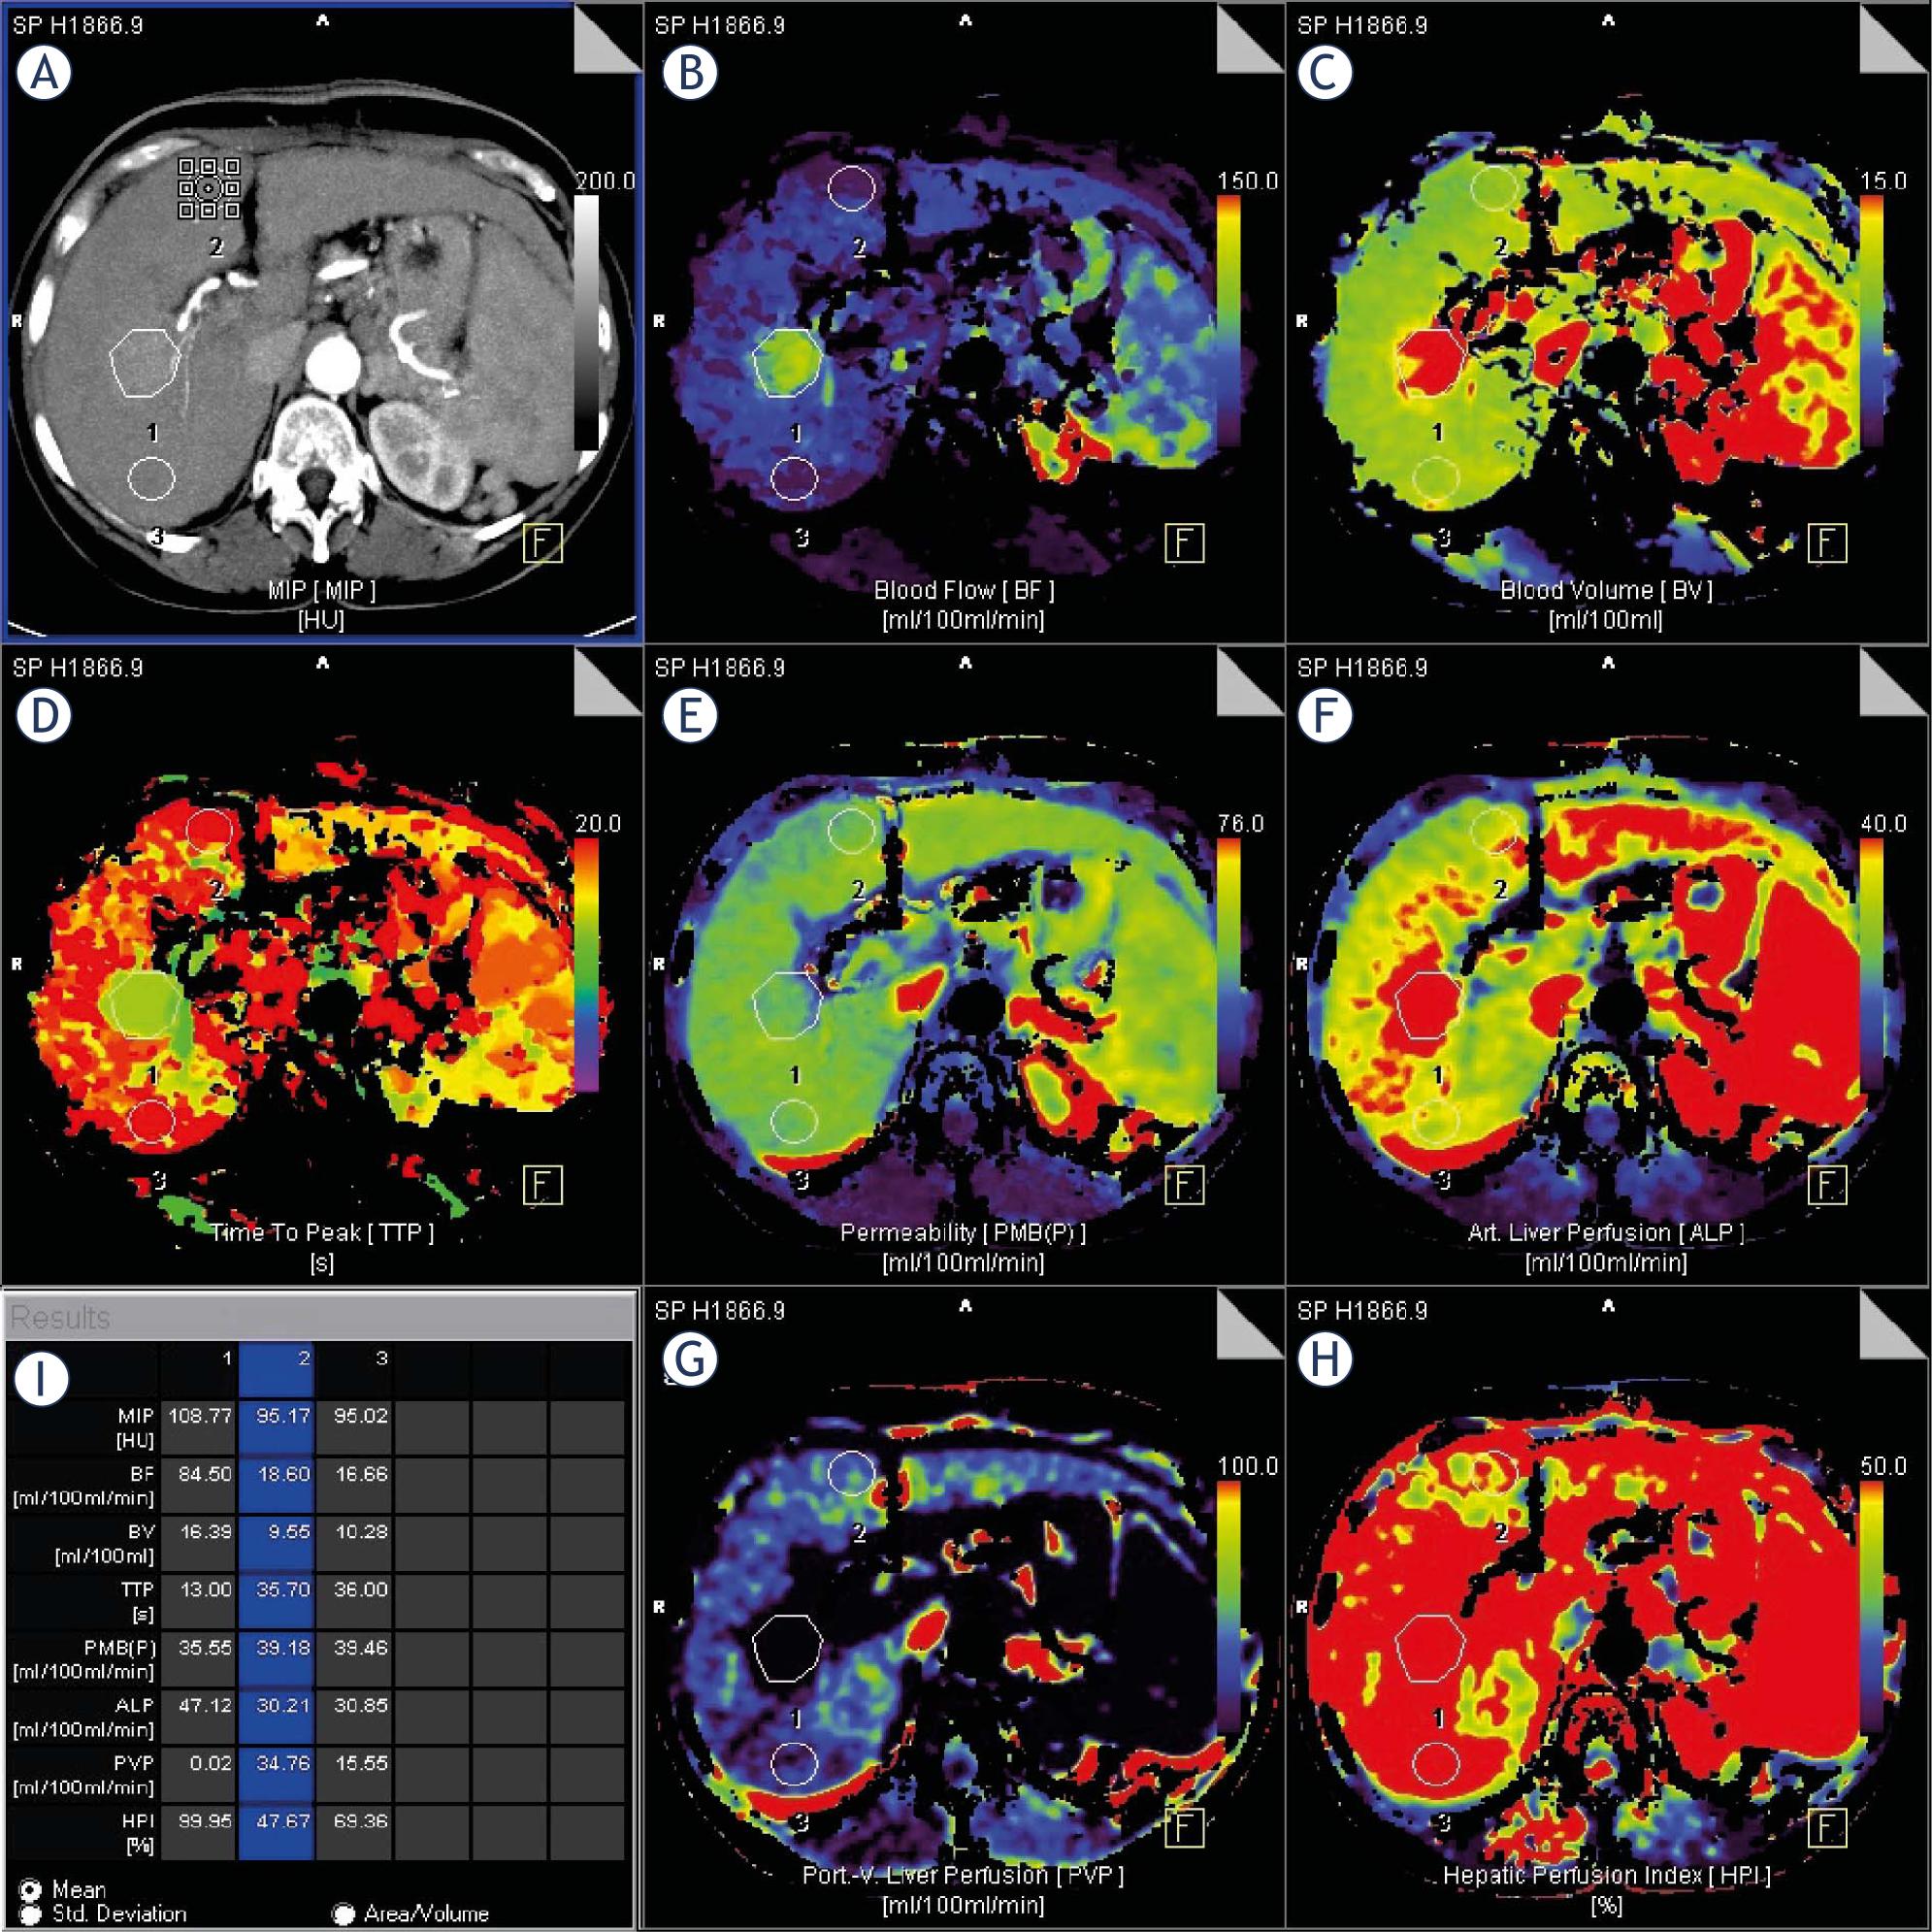

CTPI Parameters of target lesions before treatment with TACE

| Complete response (n = 9) | Partial response (n = 10) | P | |

|---|---|---|---|

| BF [ml/100ml/min] | 36.3 ± 23.2 | 51 ± 31.6 | 0.271 |

| BV[ml/100ml] | 11.6 ± 5 | 14.4 ± 4.8 | 0.240 |

| TTP [s] | 26.3 ± 8.3 | 24 ± 7.8 | 0.551 |

| PMB [ml/100ml/min] | 37.3 ± 19.3 | 33.6 ± 10.9 | 0.616 |

| ALP [ml/100ml/min] | 38.7 ± 22.2 | 49 ± 28.9 | 0.400 |

| PVP [ml/100ml/min] | 20.8 ± 22.7 | 13 ± 17 | 0.404 |

| HPI [%] | 65.1 ± 30.7 | 78.6 ± 27.4 | 0.322 |